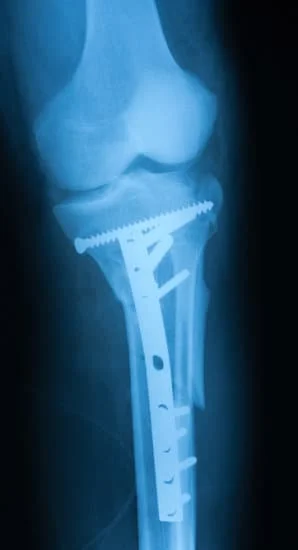

Quality and affordable healthcare has long been the essence in the field of medical sciences & treatment. Every patient expects an early diagnosis and a planned approach to treatment procedures with affordability and access to quality healthcare. Knee replacement, Hip replacement, Fracture treatment are being done by Dr.P.Sankaralingam at very affordable costs without compromising on quality.

Dr.P.Sankaralingam M.S(ortho)., DNB (ortho).,MNAMS is an experienced senior consultant Orthopaedic surgeon who does about 350 joint replacement surgeries per year in addition to treatment of Trauma cases.

Standard Hospital, Chennai’s Centre of Excellence for Orthopaedics offers minimally invasive surgeries for faster recovery.